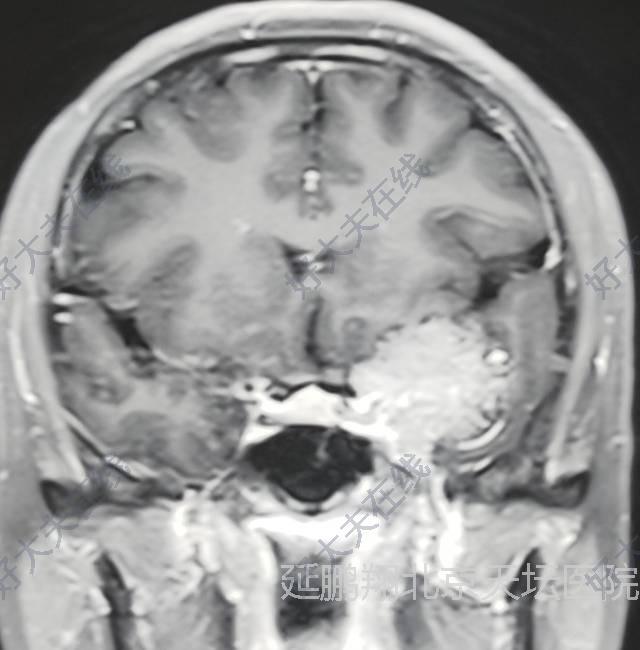

患者女性,38岁。间断性头痛3年左眼视力模糊1年。核磁显示左侧前床突脑膜瘤。

手术在全麻下进行,釆用左额颞入路,先切断肿瘤基底,阻断血供。肿瘤质地软,与脑组织粘连不紧,易分离,两者相隔有蛛网膜(图2),肿瘤切除后左侧嗅神经,视神经,颈内动脉,动眼神经均保护完好(图3)。